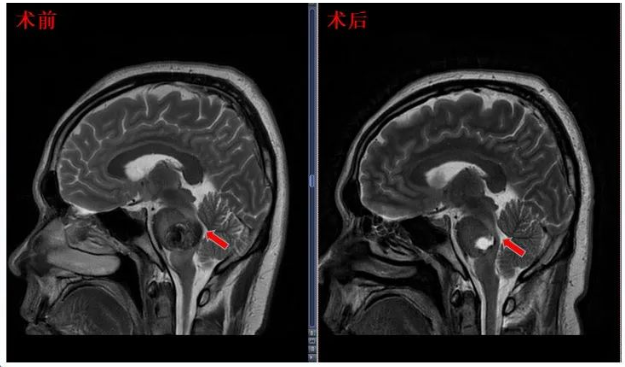

術(shù)后MRI顯示面丘結(jié)構(gòu)恢復(fù)

術(shù)前術(shù)后影像對(duì)比

術(shù)后4個(gè)月,31歲的陳先生在INC巴教授的例行隨訪中,再次得到好消息:“最近的MRI截圖。他們顯示了一個(gè)很好的發(fā)現(xiàn),完全切除海綿狀瘤而不損害周圍的腦干結(jié)構(gòu),很好了!”